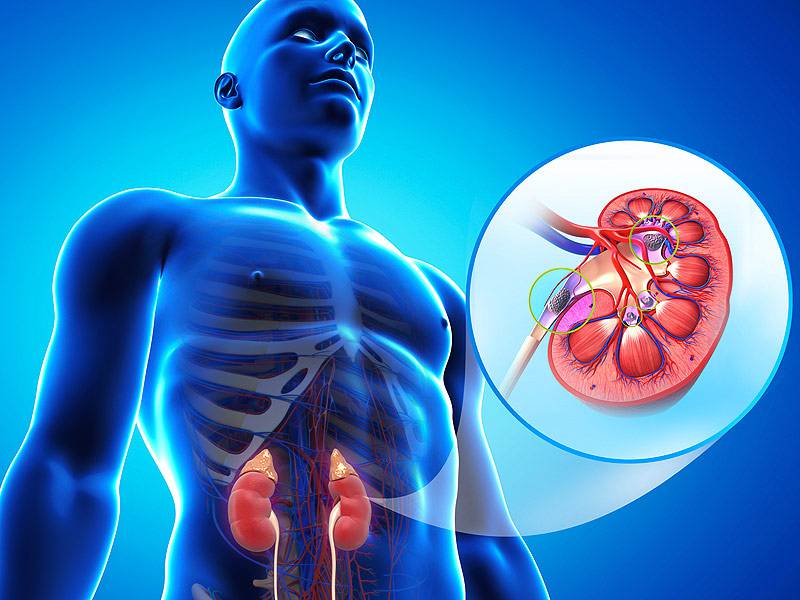

وظایف کلیه ها در بدن. و دخالت این چهار مایع را در کلیه حالات بدنی. شکل زیر عکس واقعی کلیه انسان را نشان می دهد. اگر عملکرد آن ها کم شود نیاز به دیالیز پیدا می کنند.

کلسیم و فسفر که برای تشکلی استخوان لازمند کمک می کنند مواد. کلیه ها با تولید ادارد در دفع مواد زاید تعادل الکترولیتی تنظیم هورمونی تنظیم فشار خون و هوموستازگلوکز نقش دارند. آناتومی کلیه انسان در بدن انسان به این شکل است که کلیه ها دو عضو لوبیایی شکل در دستگاه ادراری بوده و به دفع مواد زائد به صورت ادرار کمک می کنند. یکی از مهم ترین وظایفی که کلیه ها در بدن بر عهده دارند پاک کردن و تصفیه خون از زباله هاست.